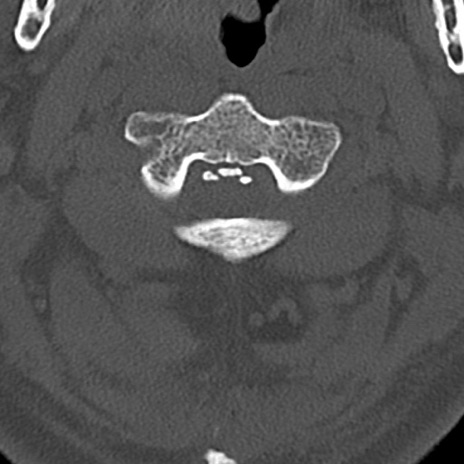

頚椎CT

横断像